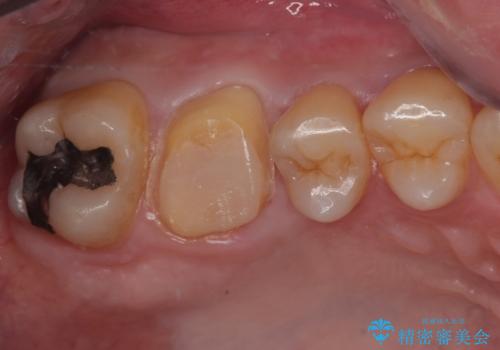

- 歯が割れたことを主訴に来院された患者様です。割れた原因としては噛み合う歯が強化セラミックスのみでできたフルジルコニアクラウンであったことと、大きな詰め物が入っていて自分自身の歯の範囲が少なかったことが考えられます。応急で来院されたときには暫間的に強力な接着剤で固定しました。

CT を撮影して確認したところ、歯肉より4ミリ程度深い場所で破折していました。患者様と相談して、外科的な介入はせずに被せもののみでの治療を行うこととしました。

拡大鏡視野下で詰め物と虫歯の除去を行い、詰め物の範囲が大きかったためオールセラミッククラウンに適した形に整えました。